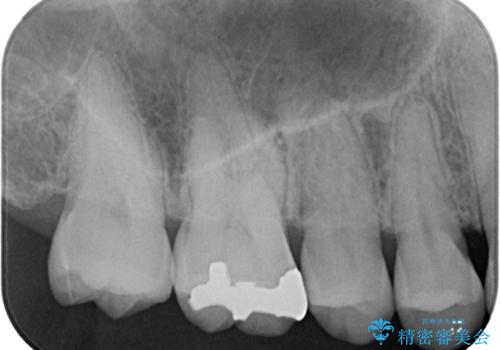

- 銀歯をやり替えたいとのことで来院された患者様です。金属の詰め物の大きさ、虫歯の範囲を考慮してセラミックの詰め物(セラミックインレー)で治療を行っていくことにしました。

拡大鏡視野下で、金属の詰め物(メタルインレー)、虫歯の除去を行い、セラミックインレーに適した形に整えました。

歯と歯の間の虫歯をコンポジットレジンや保険のメタルインレーで治すと段差ができたりして清掃性が悪くなるので、セラミックインレー修復やゴールドインレー修復などの適合の良い詰め物で治療することをオススメします。